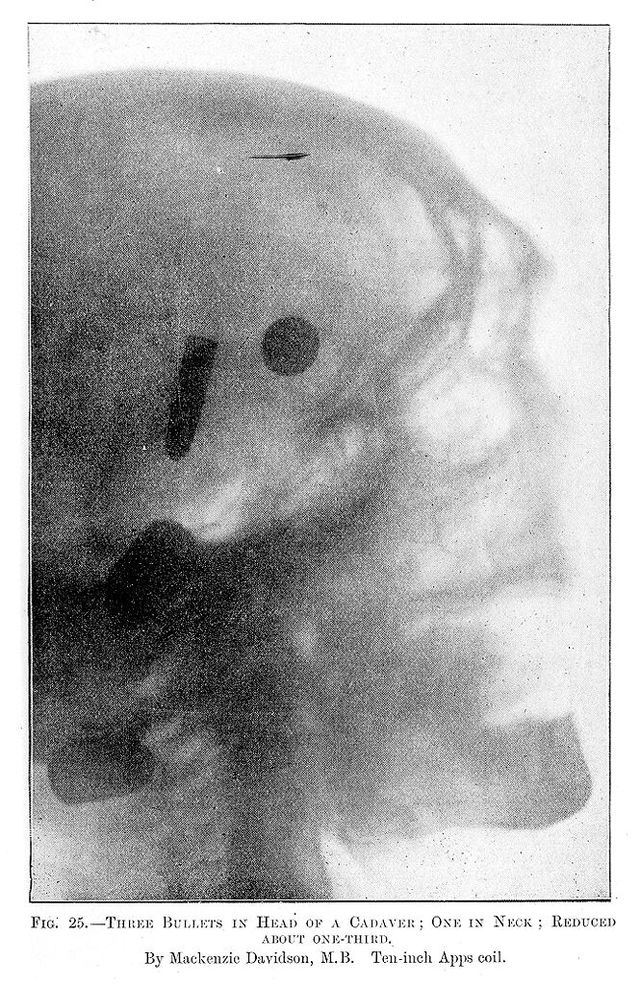

M0013195: Radiograph showing bullets in a cadaver

Credit: M0013195: Radiograph showing bullets in a cadaver. Source: Wellcome Collection.